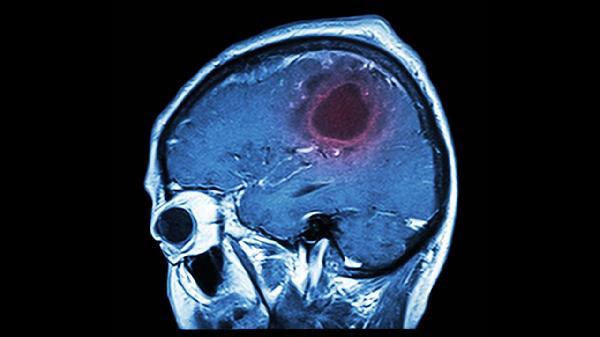

安宫牛黄丸是传统急救中成药,其成分包括牛黄、麝香、水牛角浓缩粉等,具有清热解毒、镇惊开窍的功效。临床适用于中风昏迷、脑炎、脑膜炎等疾病引起的高热神昏症状。但脑血栓属于缺血性脑血管病,病理机制为血栓堵塞血管导致脑组织缺血缺氧,与安宫牛黄丸的适应证不同。目前脑血栓的规范治疗以溶栓、抗凝、改善脑循环为主,如阿司匹林肠溶片、硫酸氢氯吡格雷片等抗血小板药物,或注射用阿替普酶等溶栓药物。